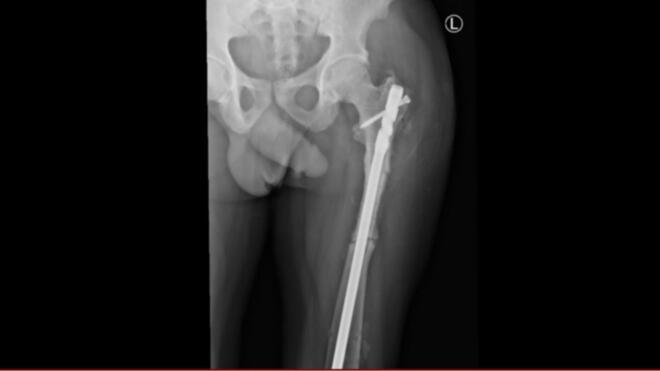

We present a 45-year-old male with adult-onset autosomal dominant osteopetrosis who sustained bilateral subtrochanteric femoral fractures-first on the right side, then on the left two years later. Both fractures were managed with intramedullary nailing (IMN). The procedures were technically demanding due to the sclerotic bone and canal obliteration, requiring sequential drilling and reaming with irrigation to prevent thermal necrosis. Both fractures healed without complications, with radiographic union at 9 months and early mobilization.

我们报告一名45岁成年男性,患常染色体显性遗传性成人骨质石化症,双侧股骨转子下骨折——右侧先发生骨折,两年后左侧发生骨折。两处骨折均采用髓内钉固定(IMN)治疗。由于骨质硬化和髓腔闭塞,手术操作技术要求高,需要依次钻孔、扩髓并冲洗以防止热坏死。两处骨折均愈合且无并发症,9个月时影像学显示骨折愈合,并可早期活动。